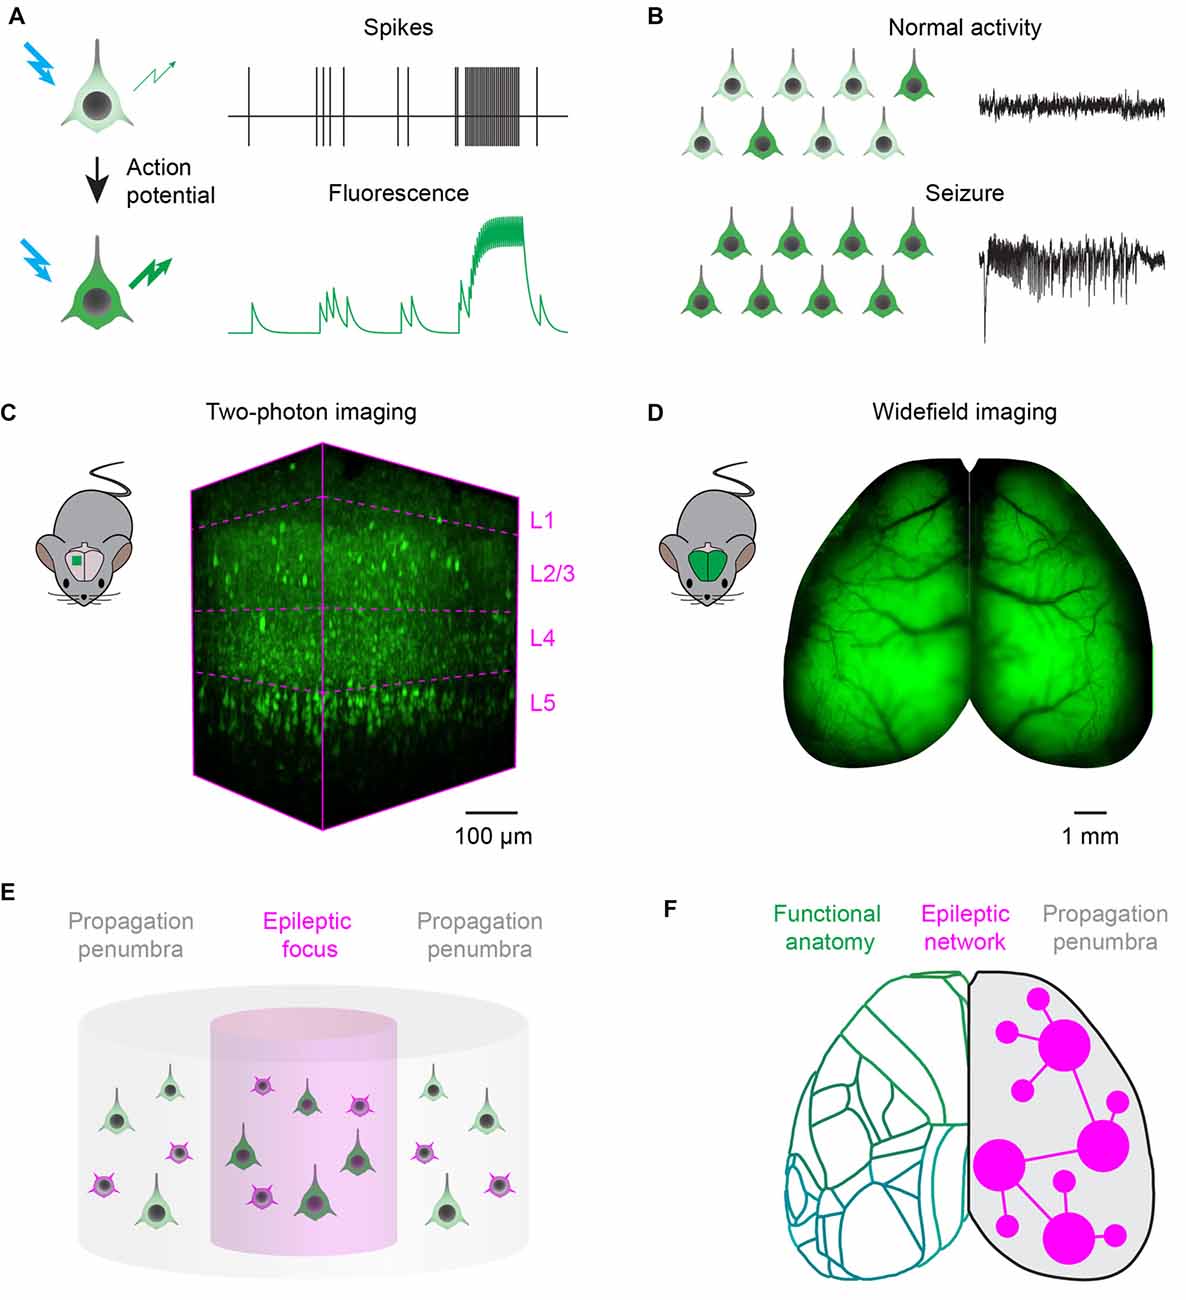

Иллюстрации из Cell Discovery: Удивительный мир науки через фотографии

Раздел: Фотоэссе